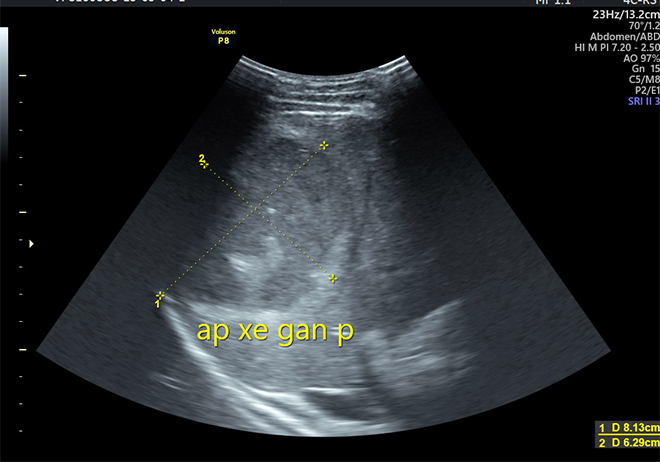

Kết quả siêu âm và chụp cắt lớp ổ bụng của anh T cho thấy nhu mô gan phải có xuất hiện khối áp-xe lớn với kích thước 8.13x6.29cm, dịch không trong, có nhiều vách, khối tổn thương nằm sát bao gan và màng phổi.

Khối áp-xe lớn với kích thước 8.13x6.29cm, nằm sát bao gan và màng phổi